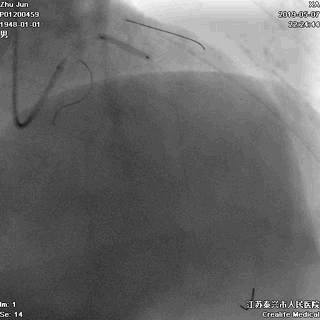

右冠状动脉无严重病变

冠脉左主干线样狭窄

回旋支主支中段闭塞

前降支开口次全闭塞